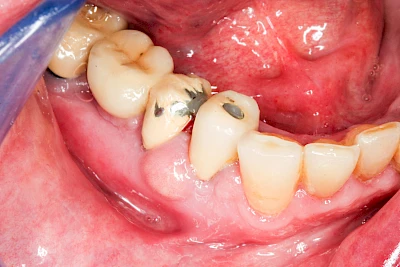

Ist zunächst nur das Zahnfleisch von der Entzündung betroffen, spricht man von Gingivitis. Später, wenn auch der Knochen um die Zähne herum entzündet ist, spricht man von einer Parodontitis. Bei der Parodontitis wird der Knochen nach und nach abgebaut und das Zahnfleisch zieht sich zurück. Die Zahnhälse und Zahnwurzeloberflächen liegen mehr und mehr frei. Die Zähne werden zunehmend lockerer und fallen schließlich aus.

Bei Implantaten – also operativ eingebrachten künstlichen Zahnwurzeln – kann der Körper die Bakterien auch nicht so gut abwehren. Hier spricht man im Fall einer Entzündung von einer Peri-Implantitis, also einer Entzündung um das Implantat herum.